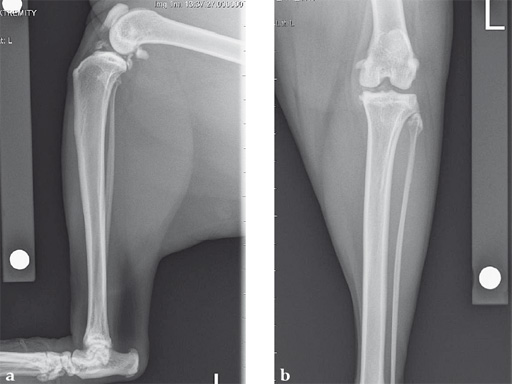

Case 1: Cocker Spaniel

(Case provided by Brian Beale, Houston, USA)

An 11-year-old female, spayed, 13.6 kg cocker spaniel had a complete tear of the left cranial cruciate ligament. A 2.4 mm TPLO plate was perfect for this dog due to the excessive slope of the tibial plateau (30) and the size of the dog. Three 2.4 mm locking screws were used proximally and three 2.4 mm cortical screws were used distally. The contour of this plate matches the contour of the bone almost perfectly. The plate is also designed to optimize the angle of the proximal screws so that they engage the most dense and thickest bone and avoids penetration of the stifle joint.